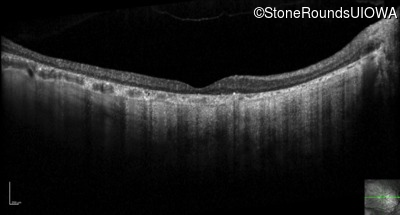

Optical Coherence Tomography - Left - 20/250 sc

Exemplar / OCT Stack

OCT Stack